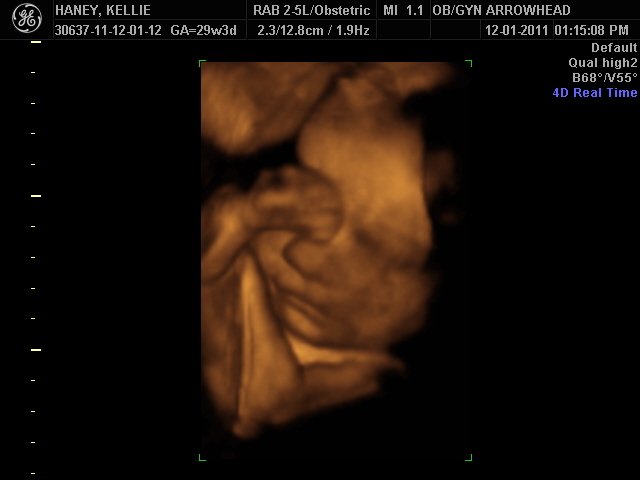

We offer complimentary 3D/4D Ultrasounds to all our OB patients around 30 weeks! The following photos are some examples of our work, shown with permission from our patients.